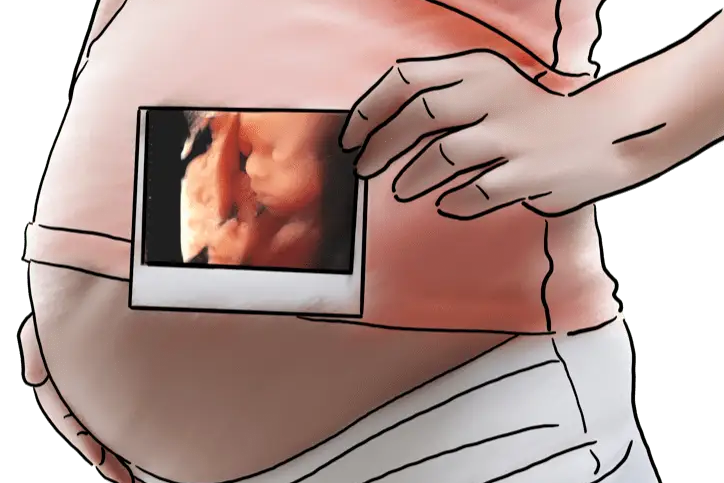

彩超提示「心室强光斑」,是不是说我的宝宝有心脏病?

胎儿心室强光斑,也叫心内强回声光点(EIF),是在超声检查时胎儿心室内出现的、与邻近肋骨回声相似或者更强的超声现象,可单发或多发,左心室多见。

胎儿心室内点状强回声

是一个声像图表现

而不是一种心脏畸形

更不是一种心脏异常诊断